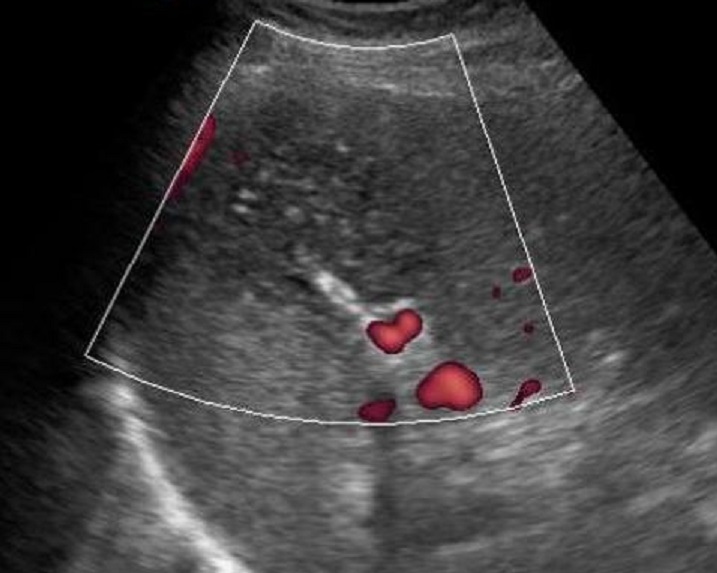

Aspect lesionnel en

forme de coin hypoechogene avec sa base peripherique orrienter

vers le versant capsulaire . Sa bord est nette ,

irregulier avec des bands claires hyperechogene .

|

Meme cas en echo Doppler en couleur

. On peut en voyant zone de infartion etre

avascularisation |